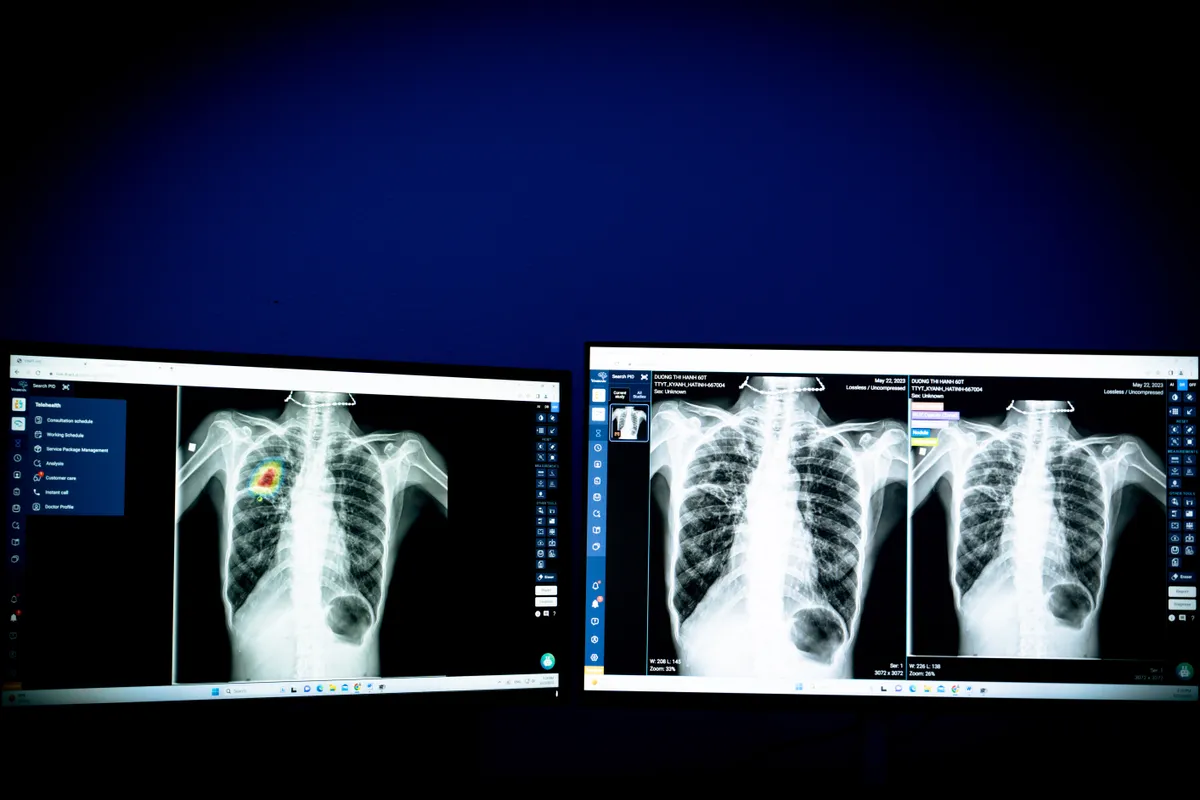

Thứ hai có thể kể đến DrAid™ X-quang ngực, là phần mềm AI giúp tầm soát tổn thương qua ảnh X-quang, đặc biệt tự động sàng lọc các bệnh lý có khả năng gây tử vong trong vòng 24 giờ như tràn khí màng phổi. Nổi bật hơn, đây là sản phẩm AI đầu tiên và duy nhất trong chẩn đoán X-quang phổi của Việt Nam và Đông Nam Á được Cục quản lý Thực phẩm và Dược phẩm Hoa Kỳ (FDA) chấp thuận vào năm 2022.

Ứng dụng AI trong lĩnh vực y tế: Bước đột phá trong chăm sóc sức khỏe con người - Ảnh 2.